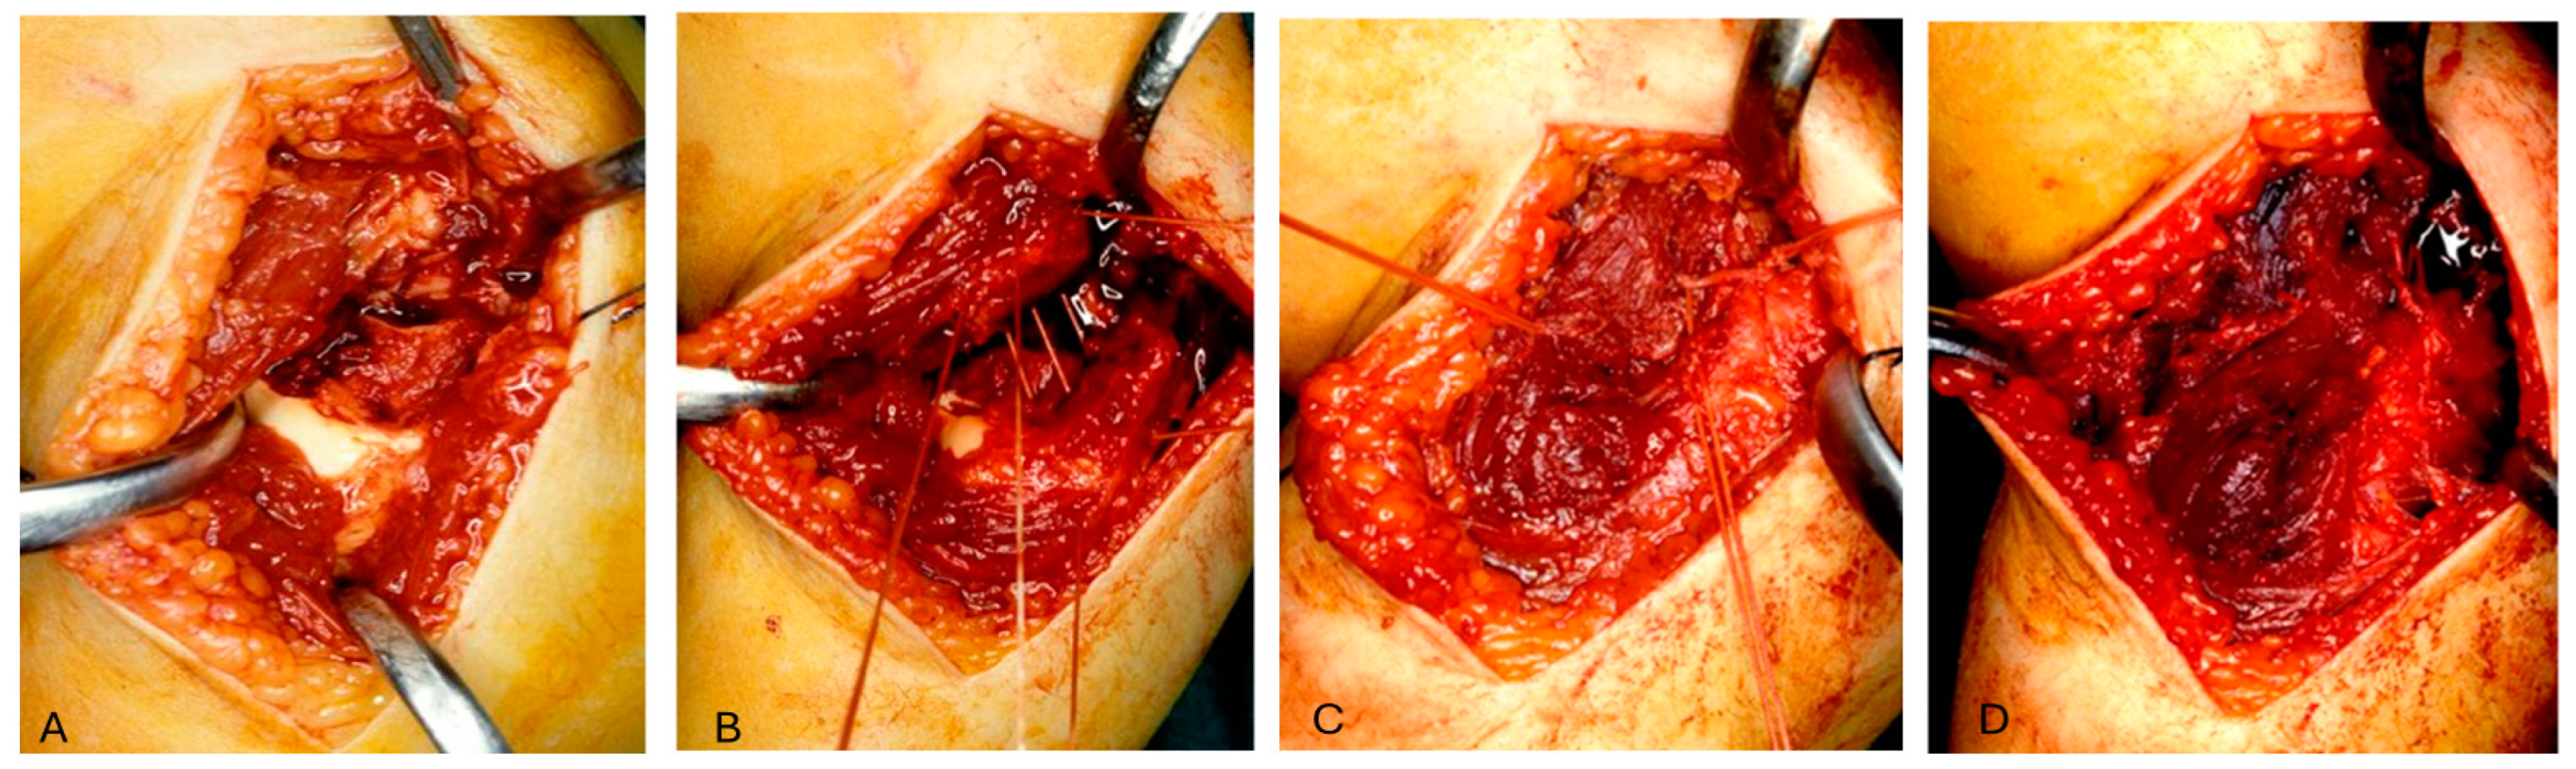

2. Materials and Methods